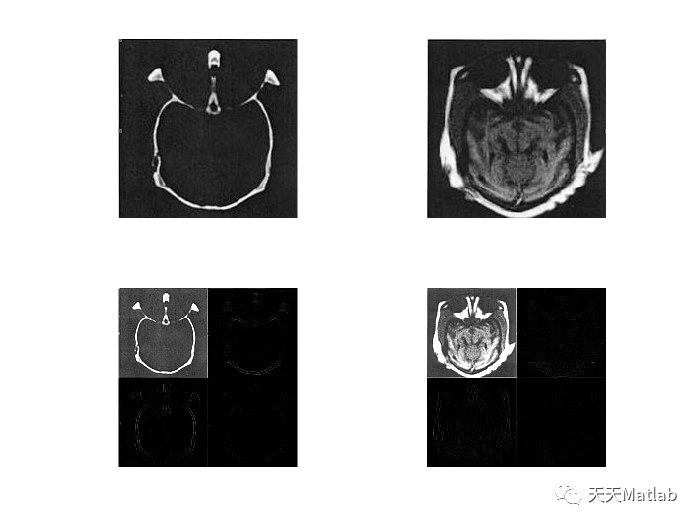

clearx1=imread('ct.jpg');subplot(221);imshow(x1);title('ct图像');x2=imread('mri.jpg');subplot(222);imshow(x2);title('mri图像');X1=double(x1);X2=double(x2);%将两幅图像进行一级db4小波变换[ca1,ch1,cv1,cd1]=dwt2(X1,'db4');subplot(223);b1=uint8([ca1 ch1;cv1 cd1]);imshow(b1);title('ct图像一级db4小波分解');[ca2,ch2,cv2,cd2]=dwt2(X2,'db4');subplot(224);b2=uint8([ca2 ch2;cv2 cd2]);imshow(b2);title('mri图像一级db4小波分解');%按照一定融合规则进行融合ca=dipinchuli(ca1,ca2);ch=PCAfusion(ch1,ch2);cv=PCAfusion(cv1,cv2);cd=PCAfusion(cd1,cd2);figure;subplot(121);imshow(uint8([ca ch;cv cd]));title('融合后小波系数');X=idwt2(ca,ch,cv,cd,'db4');subplot(122);imshow(uint8(X));title('融合后重构图像');

3 仿真结果